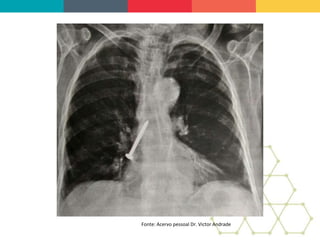

BACKGROUND: Bronchobiliary fistula

(BBF) is a rare condition in which there is

communication between the biliary

system and bronchial tree. The etiology

most commonly found is secondary to

liver or subphrenic abscesses, infected

by echinococcus or amoeba. Can occur

secondary to transdiaphragmatic

migration of the biliary stent, placed on

biliary tract for the treatment of

obstructive jaundice, and also to liver

mucormycosis. BBF was observed as

postoperative complications of liver

resection for cholangiocarcinoma. It has

also been described arising from hepatic

hydatid migration into the lung through

the diaphragm. The management of this

condition should be conducted by a

multidisciplinary team and involves less

invasive alternatives such as endoscopic

therapy and transparietohepatic

drainage.

Endoscopic treatment of bronchobiliary fistula after

liver metastasis resection: Case report

OBJECTIVE: This study aims to report a

case of a patient who developed a

bronchobiliary fistula after surgery for

liver metastasis resection of advanced

colon cancer.

CASE REPORT: Patient 53 year-old, female, diagnosed

with advanced sigmoid colon cancer with liver metastasis

and was submited a rectosigmoidectomy associated with

hepatic trisegmentectomy. In the immediate postoperative

period, the patient developed a high-output biliary fistula

associated with choleperitoneum and subsequent

formation of subphrenic abscess drained externally.

Referred to our service for performing endoscopic

retrograde cholangiopancreatography (ERCP) by default

of obstructive jaundice and bilioptysis in moderate

quantity. The diagnosis of BBF was showing the

cholangiography and then confirmed by computed

tomography of the chest and abdomen. The endoscopic

treatment consisted of drainage of the bile duct; the

decompression was realized through wide papillotomy and

passage of a plastic biliary stent.

CONCLUSION: ERCP is a minimally invasive procedure

and choice in the treatment of bronchobiliary fistula with a

success rate close to 60%. The literature demonstrates

resolution of the fistula, with conservative treatments,

around five weeks. The patient progressed satisfactorily

with bilioptysis resolution and decrease the bilious flow

through the external abdominal drainage. A bronchoscopy

was performed after 15 days and did not show the

presence of bile secretion in the bronchial tree. In the

follow up of outpatient, didn't occurs any sign of

recurrence of the bronchobiliary fistula.